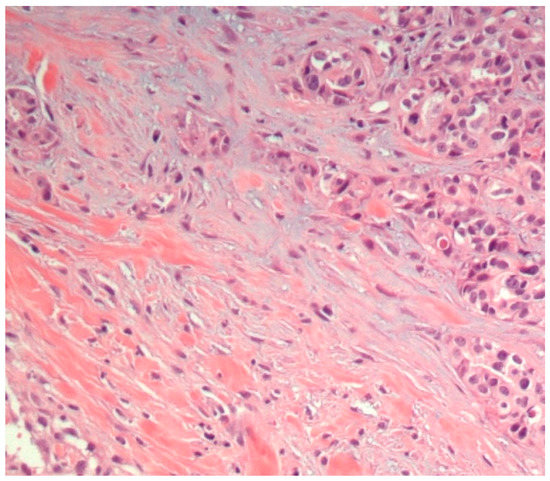

3.1. Histopathological Assessment